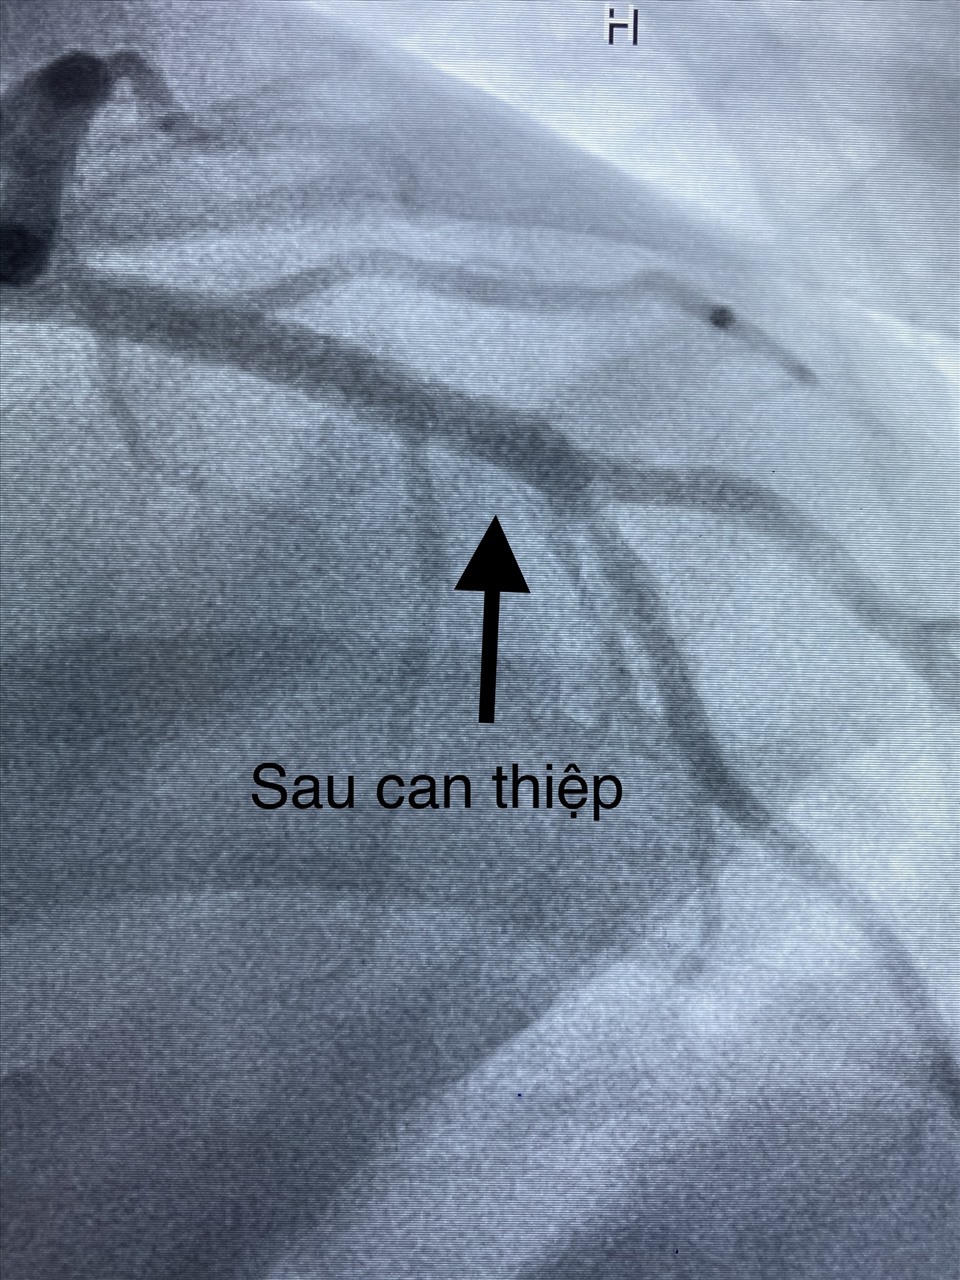

Hình ảnh động mạch vành của bệnh nhân bị ngưng tim trước khi can thiệp. Ảnh: Bệnh viện cung cấp

Hình ảnh động mạch vành sau khi can thiệp. Ảnh: Bệnh viện cung cấp

13 giờ 30 phút cùng ngày nhập viện, bệnh nhân được chỉ định chụp và can thiệp mạch vành cấp cứu. Kết quả hẹp nhánh liên thất trước đoạn II 80%, san thương không ổn định và can thiệp thành công bằng Stent phủ thuốc trong vòng 20 phút. Bệnh nhân sau can thiệp được chuyển đến Khoa Hồi sức tích cực - Chống độc theo dõi và điều trị tiếp. Dựa vào các xét nghiệm, bệnh nhân được lọc máu liên tục cấp cứu suy đa tạng và kết hợp sử dụng hệ thống thăm dò huyết động theo phương pháp PICCO.